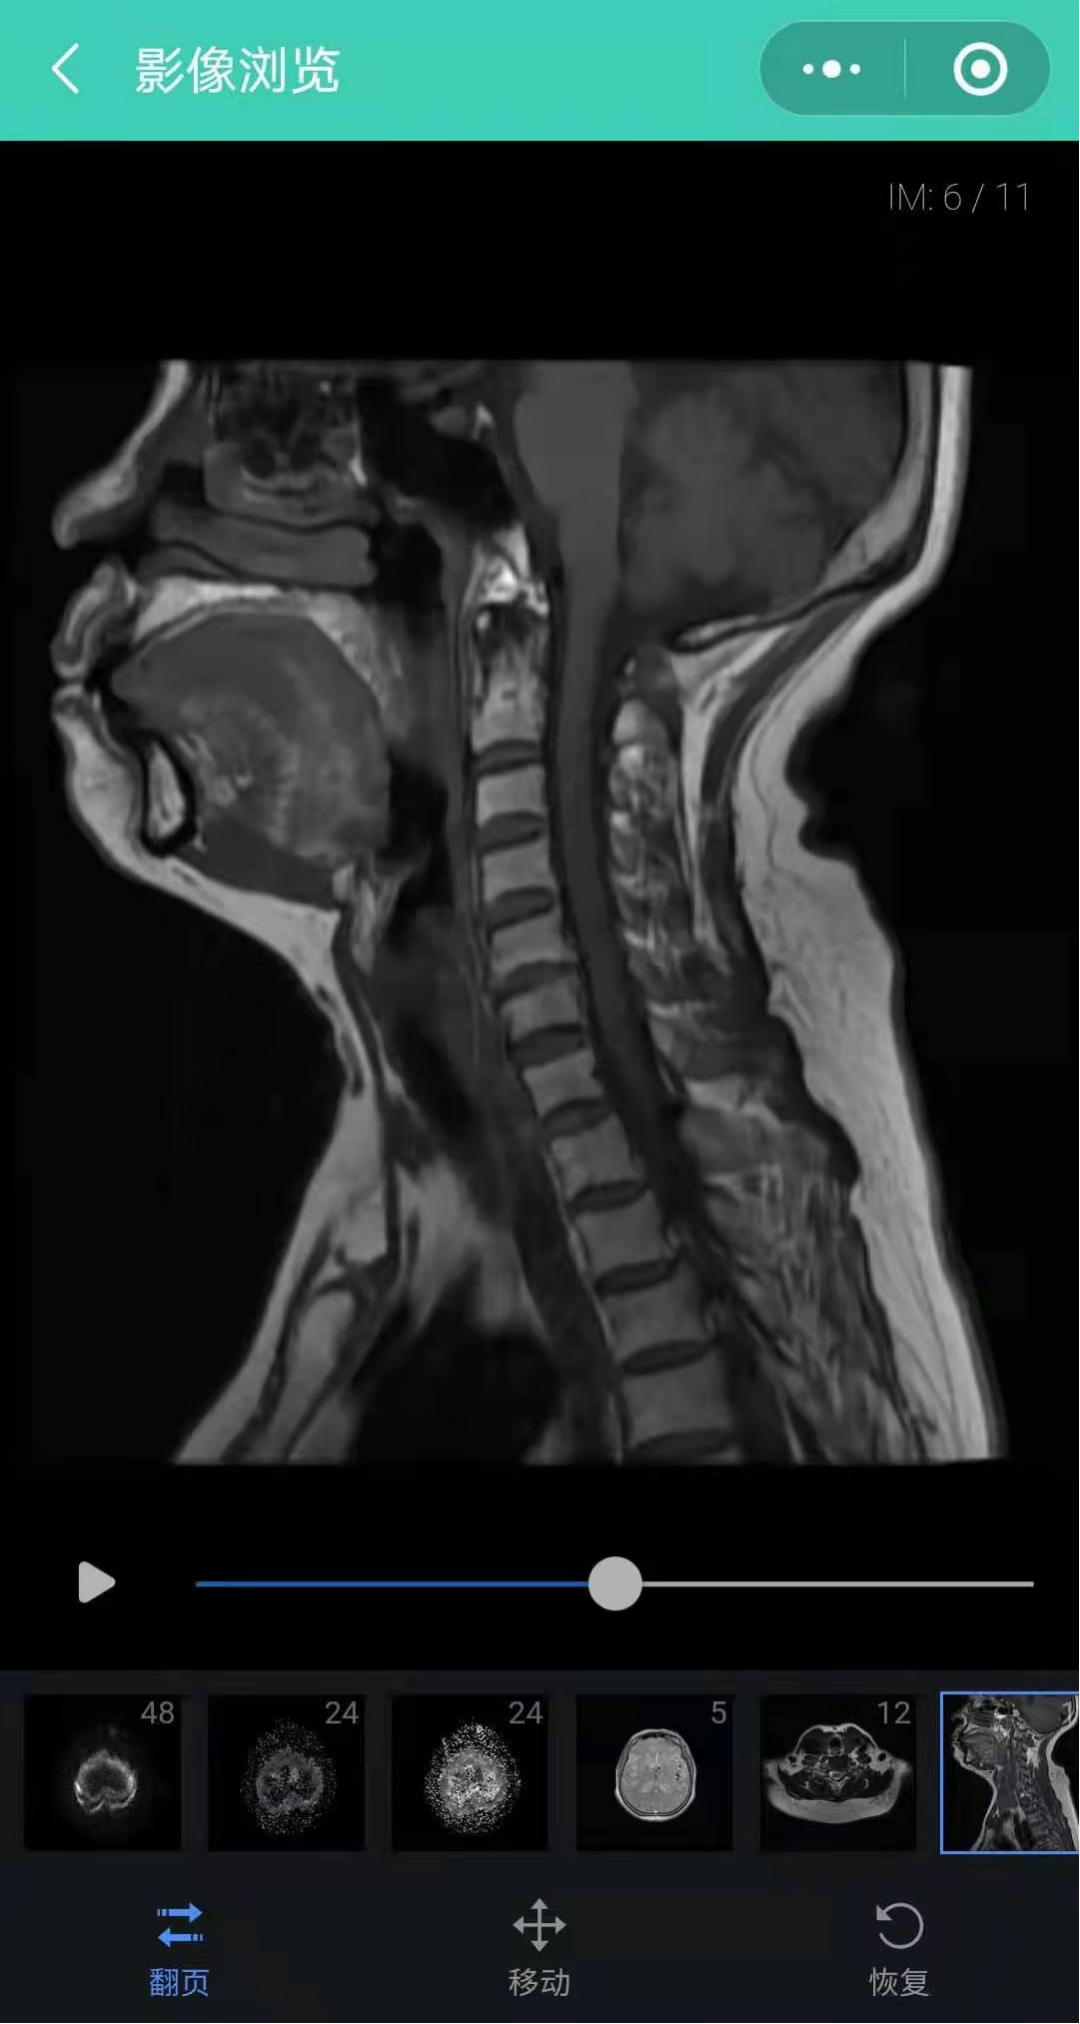

影像浏览,点击影像浏览查看影像,影像进行放大、移动、播放等细节查看;